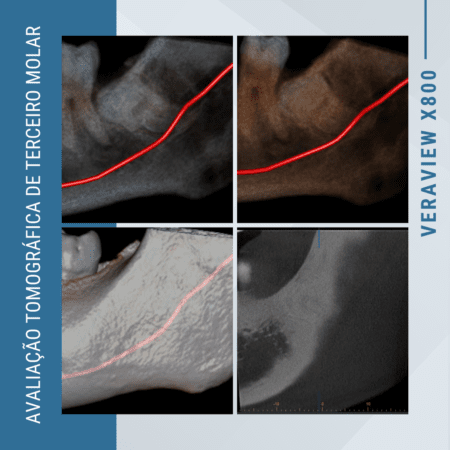

Análise Tridimensional de Perda Óssea precisão no diagnóstico e tratamento

Para dentistas comprometidos com diagnósticos precisos e tratamentos efetivos, a tomografia de alta resolução se apresenta como um recurso inestimável, especialmente na avaliação detalhada da